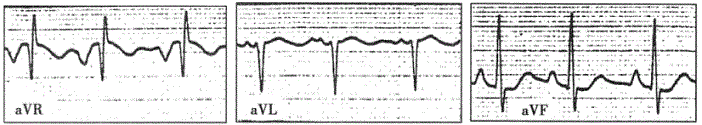

问题 患者女性,40岁,风湿性心脏病,二尖瓣狭窄合并关闭不全。心电图如下图所示,提示

选项 A.双侧心房和双侧心室肥大 B.右心室肥大 C.左心房和右心室肥大 D.双侧心房肥大 E.双侧心室肥大

答案 A

解析 :心电图显示窦性心律,心率约90次/分。Ⅱ、aVF导联P波高尖,振幅>0.25mV;V导联P波振幅的算术和>0.2mV,均提示右心房肥大。另外,Ⅰ、aVL、V导联P波增宽伴切迹,提示左心房肥大。心电轴右偏>+90°,V导联呈R型,V导联S波加深,R+%>1.2mV,V导联ST段压低及T波倒置,均为严重右心室肥大的心电图表现。本图V导联R波振幅≥2?5mV(注意:图中V5导联记录电压减半),结合患者有二尖瓣关闭不全病史,提示还可能存在左心室肥大。